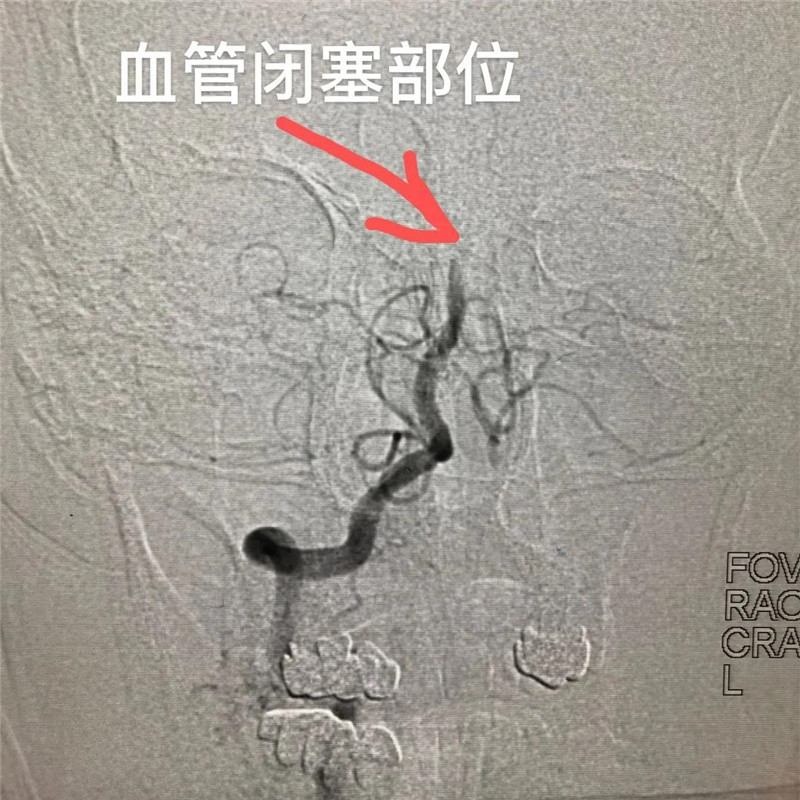

血管闭塞影像

晚上10点04分,高度怀疑为急性脑梗死的吴伯经大塘医院对症处理后,被送至我院急诊科,根据紧急进行的心电图和CT检查结果,陈淦副主任医师与急诊科医生会诊初步诊断吴伯为急性脑梗死,有溶栓适应症。10点38分,吴伯被送到总院的第34分钟(标准为60分钟内),实施了静脉溶栓治疗,但效果不佳。急诊行头颈CTA检查发现吴伯基底动脉闭塞,在获得家属同意后,我院卒中中心启动绿色通道,专家团队、介入室开始手术准备。